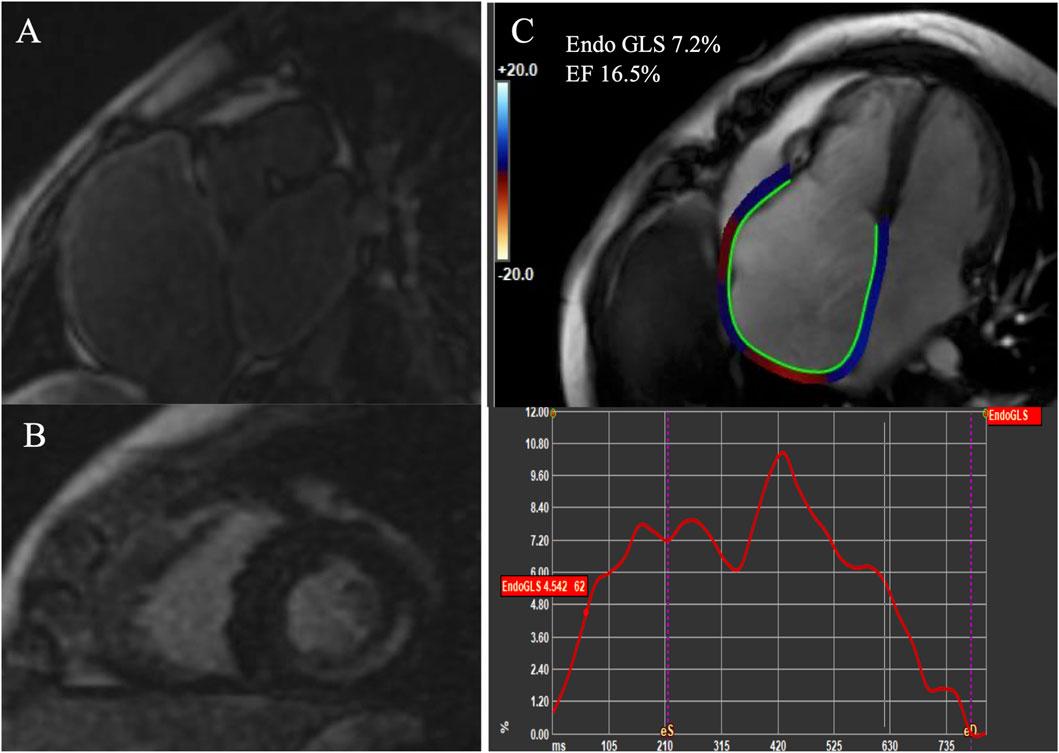

Left ventricle fibrosis was found in patient 1 and 3, involving the basal and mid-inferolateral segments in patient 1, and the basal inferior and basal inferolateral segments in patient 3 (Figure 2). Bi-atrial fibrosis was present in patient 1 and 2. The LA strain was reduced in all patients with a greater reduction in patient 2 and patient 3. Moreover, the LA EF was severely reduced in patient 1 and 2, mildly reduced in the patient three probably due to the absence of fibrosis at atrial level. The RA EF was severely reduced in the patient 1 and patient 2 but less impaired in patient 3.

Figure 2

MRI images showing cardiac sections labeled A, B, and C. Image A displays bi atrial view with LGE. Image B presents a short-axis view with left ventricle LGE. Image C features right atrial strain analysis with color-coded strain lines and a graph showing strain values over time. The text

Figure 2. CMR data (A) Bi atrial LGE; (B) Left ventricle LGE; (C) RA strain of patient 2. LGE Late gadolinium enhancement, RA right atrial.